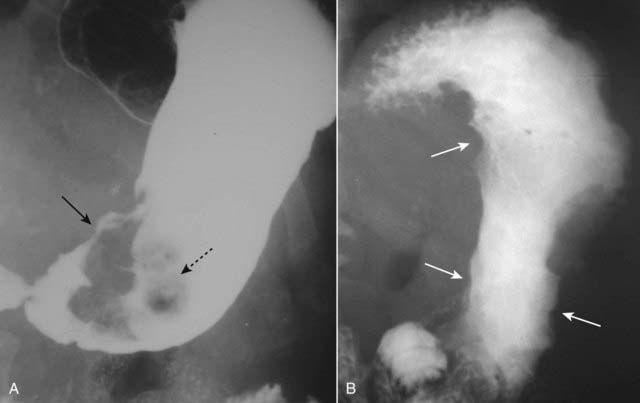

Figure 18-18 Intussusception, barium enema, and CT scan.

A, When one loop of bowel prolapses inside the loop immediately distal to it, the resultant obstruction produces a coiled-spring appearance on barium enema examination as two loops of bowel are superimposed on one another (solid white arrow). B, In another patient with an intussusception, a loop of large bowel (solid white arrow) is seen prolapsing into the loop distal to it (solid black arrow) producing a filling defect and obstructing the lumen.

image Occasionally, a polyp may serve as a lead point for an intussusception, in which the polyp drags and prolapses one part of the bowel into the lumen of the bowel immediately ahead of it. The bowel proximal to the intussusception is usually obstructed and dilated. Intussusception may produce a characteristic coiled-spring appearance on barium enema or CT (Fig. 18-18).